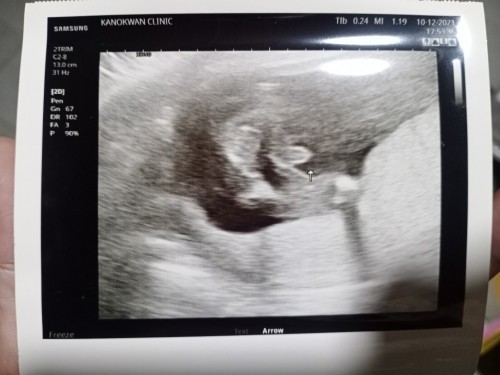

เจ้าจิ๋ว ตอน 9 Week ค่ะ ตอนนี้ได้13weekแล้วค่ะ❤️❤️